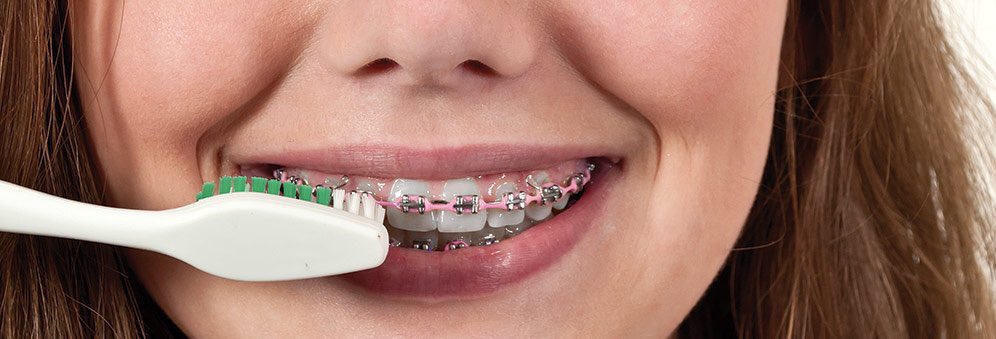

الوقاية:

٩- الاشخاص الذين يستعملون الأجهزة التقويمية يجب أن يراعو عناية فائقة بالأسنان واللثة لوجود اجهزة يعلق بها كمية أكبر من البلاك وبالتالي تضاعف عدد البكتيريا المسببة للتسوسات والتهابات اللثة (٩)=